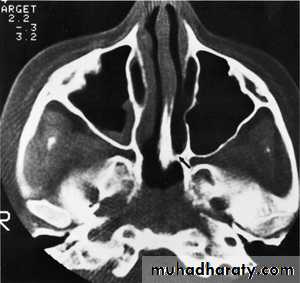

SAH

White sulciOpacified IHF